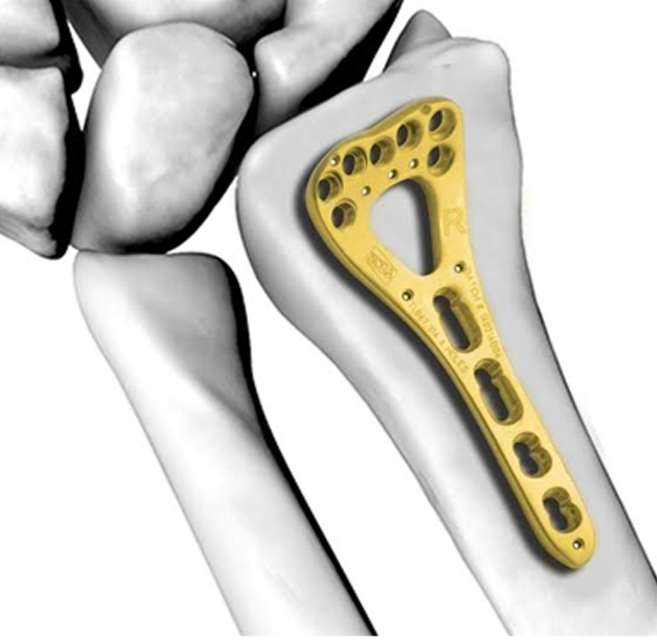

• What are the implants we use for fracture fixation?

Implants are made from metal most commomly stainless steel or titanium. Depending on the fracture configuration and the bone we use

• Plates and screws

• Nails or Rods

• Wires/Pins

• External Fixators